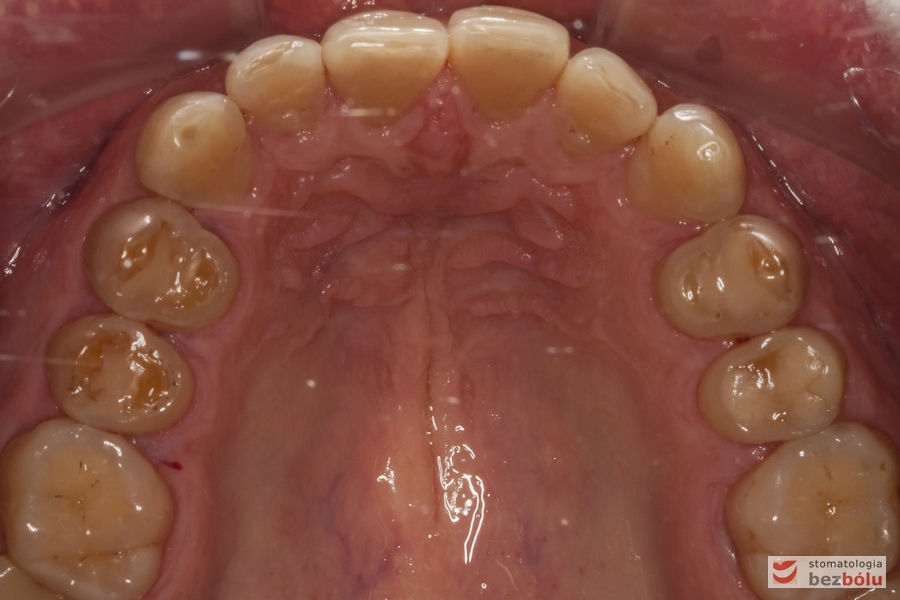

Szczęka - widok okluzyjny, liczne starcia i ubytki szkliwa, nieregularna obwiednia łuku

Szczęka – widok okluzyjny, liczne starcia i ubytki szkliwa, nieregularna obwiednia łuku